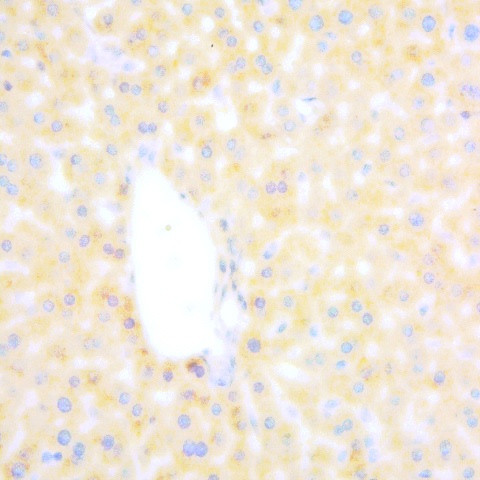

Hepatitis B virus core Ag Antibody (500-1704) in IHC (P)

Immunohistochemistry: Human Liver carcinoma (FFPE) stained with Rabbit anti-HBV core antigen (Cat#500-1704 ) at 1:200 for 10 min @ RT. Staining of formalin-fixed tissue requires boiling tissue sections in 10 mM Citrate Buffer, pH 6.0 for 10 min followed by cooling at RT for 20 min. {{ $ctrl.currentElement.advancedVerification.fullName }} 验证信息 View more